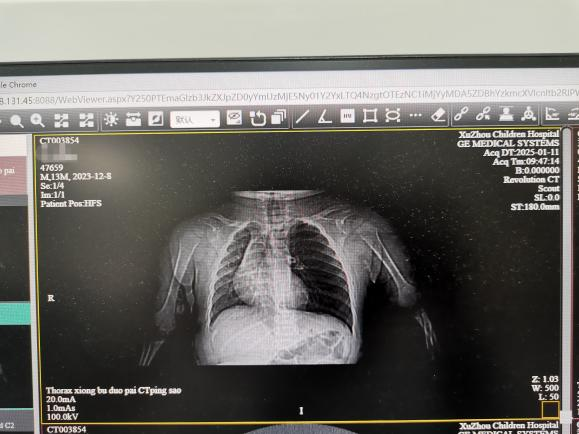

幸运的是,经过两三天的治疗,小宝宝的病情明显好转,体温正常了,咳嗽和气喘也减轻了,呼吸也平稳了。现在,心电监护和吸氧都可以撤掉了,小宝宝终于可以去做影像学检查了。因为小宝宝有反复咳嗽、气喘的病史,这次病情又来势汹汹,还合并了甲型流感病毒感染,陈医生决定给他做胸部CT检查。

检查结果一出来,放射科就急急忙忙地打电话来报危急值。原来,CT报告显示小宝宝的左侧支气管里可能有异物。异物在呼吸内科并不罕见,小孩子吃东西时容易呛到,有时候家长喂食瓜子、花生时,孩子一呛咳,东西就可能掉进支气管里。支气管里的异物会引起反复咳嗽、喘气,甚至堵塞气道,引起肺不张,划破气道黏膜还会咯血、甚至支气管穿孔。在临床上,支气管异物属于危急情况,需要立即报告。